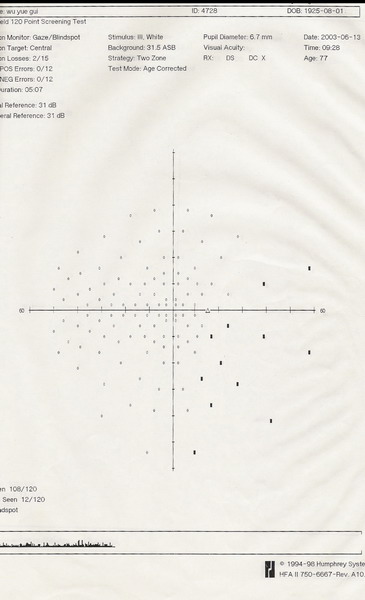

2003年6月13日视野(左、右)